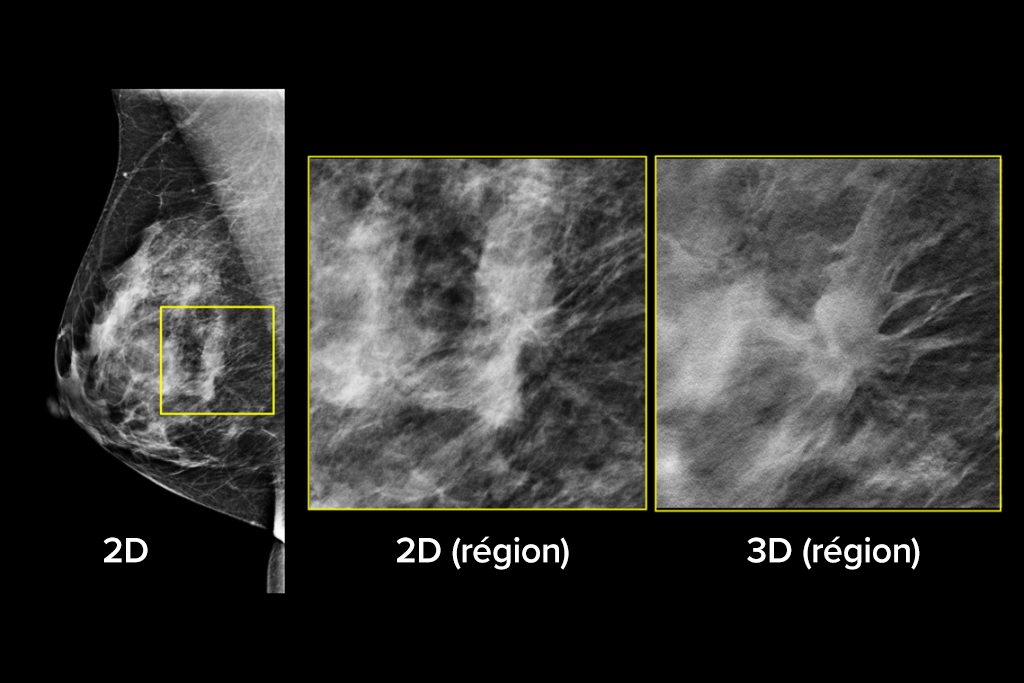

Images cliniques

Images cliniques d’une mammographie

Images cliniques d’une mammographie avec lésion suspecte

Le système de mammographie 3Dimensions fonctionne avec la toute dernière technologie de tomosynthèse intelligente, qui combine l’imagerie haute résolution Clarity HD™, l’imagerie synthétique Intelligent 2D™ et 3DQuorum™ SmartSlices pour un flux de travail efficace.